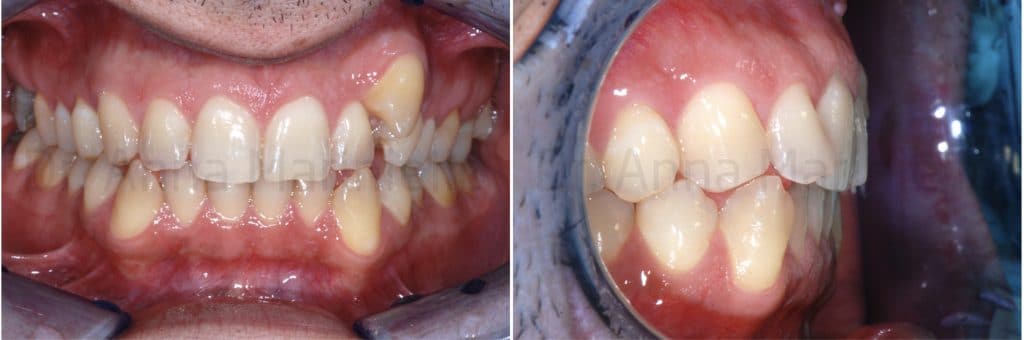

The patient, came to our attention, had a malocclusion characterized by:

- First class molar and canine on the right;

- Second class molar on the left;

- Complete absence of space for the left ectopic buccal canine;

- Upper and lower teeth crowding;

- Upper midline shifted 2,5 mm to the left;

- Overbite of 1 mm for 12, 3 mm for 11 and 21, 0 mm for 22.

- Overjet of 2,5 mm for 12, 2 mm for 11 and 21, 0 mm for 22.